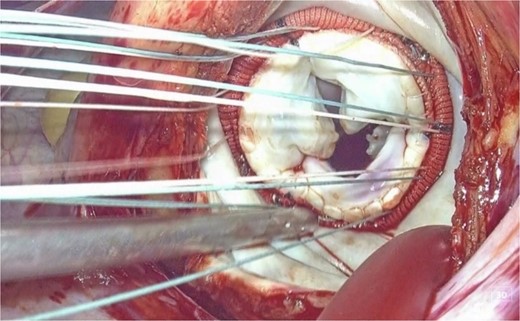

We planned totally endoscopic MVR using a 3D endoscope without robotic assistance. Preoperatively, all equipment was arranged in a mirrored fashion. After double-lumen endotracheal intubation of general anesthesia, a central venous catheter was inserted into the right jugular vein, and a superior vena cava venous drainage cannula and a temporary ventricular pacing catheter were inserted into the left jugular vein. After heparinization, an arterial cannula and an inferior vena cava venous drainage cannula were inserted into the left femoral artery and vein, respectively, to establish cardiopulmonary bypass (CPB). A 4-cm left thoracotomy was performed in the fourth intercostal space (ICS). A 10-mm trocar for the 3D endoscope (Karl Storz) was inserted through the third ICS, and a 5-mm port for right-handed instruments was placed in the second ICS. Left-handed instruments were inserted through the main incision, and the procedure was performed using a three-port system centered on the 3D endoscope (Fig. 2). After cardiac arrest was achieved, the mitral valve was exposed and replaced using standard techniques. The Epic 29 mm bioprosthetic valve was sutured using the Cor-Knot surgical tying device. Weaning from CPB was uneventful (CPB time and cross clamp time was 132 and 84 min, respectively). The patient was recovered uneventfully.

Appearance of the intraoperative surgical field: Setup of the simplified three-port system with 3D endoscopy.

This is believed to be the first report of a totally 3D endoscopic mitral valve replacement in SIT. We have demonstrated that totally endoscopic surgery is feasible in cases of SIT and that its advantages can be offered to the patient. Several precautions were necessary for the success of this procedure given the anatomy of SIT. The first was the placement of the surgical instruments under the preoperative mirror image. All settings, positions, and instruments must be placed in opposite directions, and the cannulation sites must be completely opposite. The second is to adapt to the inverted left–right anatomy of the thoracic cavity. It is important to note that the main incision in the fourth ICS is on the left side of the mitral valve, contrary to the usual approach. This means that needles and sutures, prosthetic valves, and other devices are inserted through the main incision on the left side toward the mitral valve using a left-handed forceps; if we are right-handed, we must switch the needle threads to a right-handed needle holder in the thoracic cavity for each suture (Figs 3 and 4).

3D endoscopic view of the intraoperative field: Sutures, prosthetic valves, and the Cor-Knot surgical tying device are inserted through the main incision on the left side toward the mitral valve.